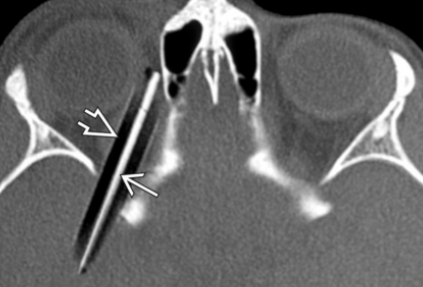

Metal

• Densité >1’000 HU